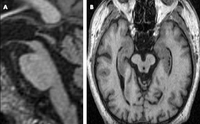

Progressive supranuclear palsy

MRI of the brain in a patient with clinically diagnosed PSP. Image A: sagittal T1-MRI through the brainstem demonstrates atrophy in the midbrain with relative preservation of the pons, giving the appearance of a hummingbird. Image B: on axial T1-weighted imaging, the dorsal midbrain is reduced in volume, giving a “Mickey Mouse” appearance

Schott JM. Practical Neurology 2007; 7: 186-190; used with permission